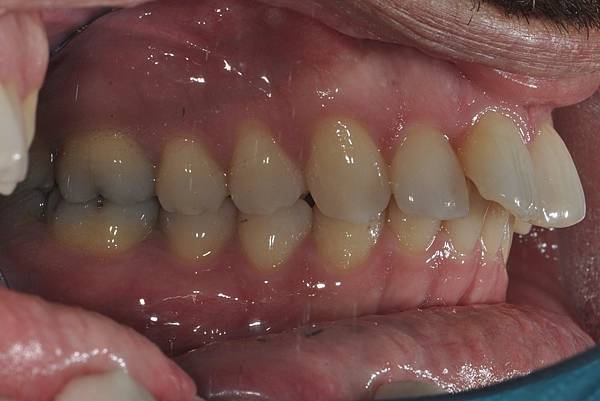

台灣的牙科醫療品質, 連外國人都說讚!此案例為深咬合併二級咬合 林醫師藉由正中上顎骨釘(HPPG technique)做上顎全齒列後移改善暴牙 讓本來五官就相當立體的艾先生,笑起來更燦爛了! 治療前/治療後-以上案例由林昇進醫師提供 分享到